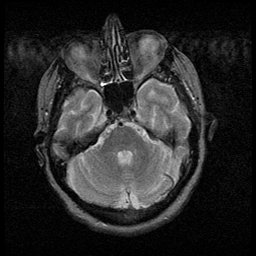

Huntington's Chorea, MR -- Slice #4

[Home][Help][Clinical] Slice 4